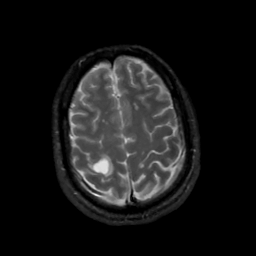

MR Study #5, March 10, 1991 -- Slice #41